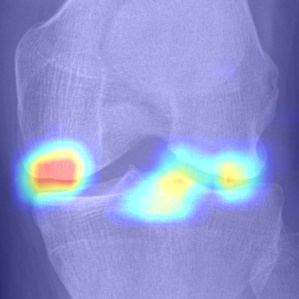

Refer to caption

(a) DenseNet-201

(b) ResNet-18

(c) VGG-11

(d) Tiuplin et al. [12]

(e) Wang et al. [16]

(f) Our model

Figure 8: Comparison of attention maps obtained from the last layer using different learning models.

To visualise the regions that contributed to the decision of each model, the Grad-Cam technique [36] was used. The attention maps obtained are presented in Fig. 8. As can be noticed, all evaluated models show a certain sensitivity to regions that involve early KOA (KL-2) characteristics (osteophytes and JSN). However, DenseNet, ResNet, and VGG models also exhibit a reaction to background noise, which may negatively impact the classification performance. To a lesser extent, the Siamese-based models [12] and [16] exhibit more reaction to areas affected by OA. Conversely, our proposed approach focuses more on regions affected by OA, which demonstrates that with a well-designed position embedding layer, it is possible to make the model concentrate on specific areas concerned by OA. It is noteworthy that during the data preprocessing of Siamese-based networks ([12] and [16]), it is often necessary to crop key patches as an input pair to the network. While this significantly reduces the parameter size of the model, it results in a loss of information from the input image. Especially for medical images, the integrity of global image information is vital and can enhance the model’s decision confidence in clinical applications. In comparison to those methods, our approach simply encourages the model to pay more attention to the key patches, but it also considers the texture information of other patches to some extent. Additionally, thanks to the ordered position embedding of key patches, our model handles their sequential information better. As can be seen in Fig. 8(d) and Fig. 8(e), compared to [12] and [16], our model is able to draw attention to locations of possible osteophytes in the joint space, which is more consistent with medical opinion.